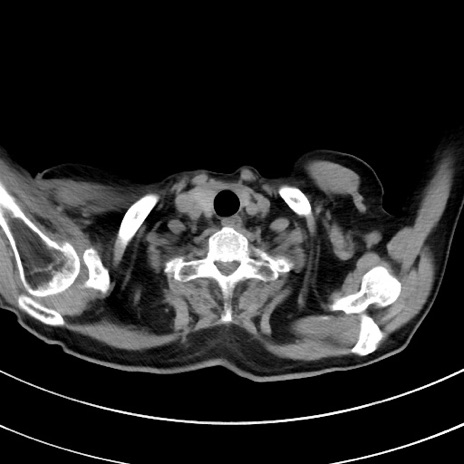

症例33(横断像)

【症例】70歳代 女性

【主訴】心窩部痛

【現病歴】延髄病変の精査・加療にて神経内科入院中。本日より心窩部痛あり。

【身体所見】右下腹部を中心に圧痛と反跳痛あり。